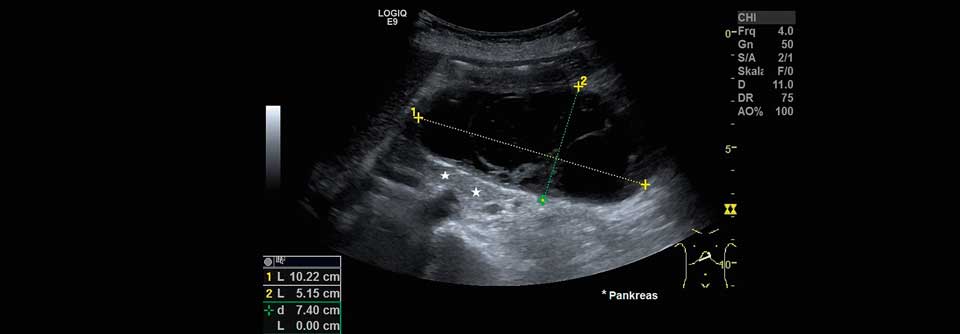

Werden keine Ursachen für eine akute Pankreatitis gefunden, wird sie als idiopathisch gewertet. Dabei lassen sich in vielen Fällen doch Auslöser finden – wenn man richtig sucht.

Die idiopathische Pankreatitis ist zwar ein leidiges Thema, gab Professor Dr. Peter Layer vom Israelitischen Krankenhaus Hamburg zu. Doch sie sei wahrscheinlich fast die wichtigste Form der Erkrankung und bedürfe großer Aufmerksamkeit. Denn in vielen Fällen findet man eben doch eine Ursache für die Beschwerden.

Jüngere sollte man ggf. auf genetische Mutationen untersuchen. Bei Älteren kann es lohnen, sich auf Tumorsuche zu begeben. In einer prospektiven Kohortenstudie mit 176 Patienten, die an einer vermeintlich idiopathischen akuten Pankreatitis litten, wurde im Rahmen weiterführender Untersuchungen bei immerhin 7 % eine Neoplasie entdeckt. Eine biliäre Ursache fand sich sogar in 22 % der Fälle. Bei weiteren 7 % konnte man andere Auslöser sichern.